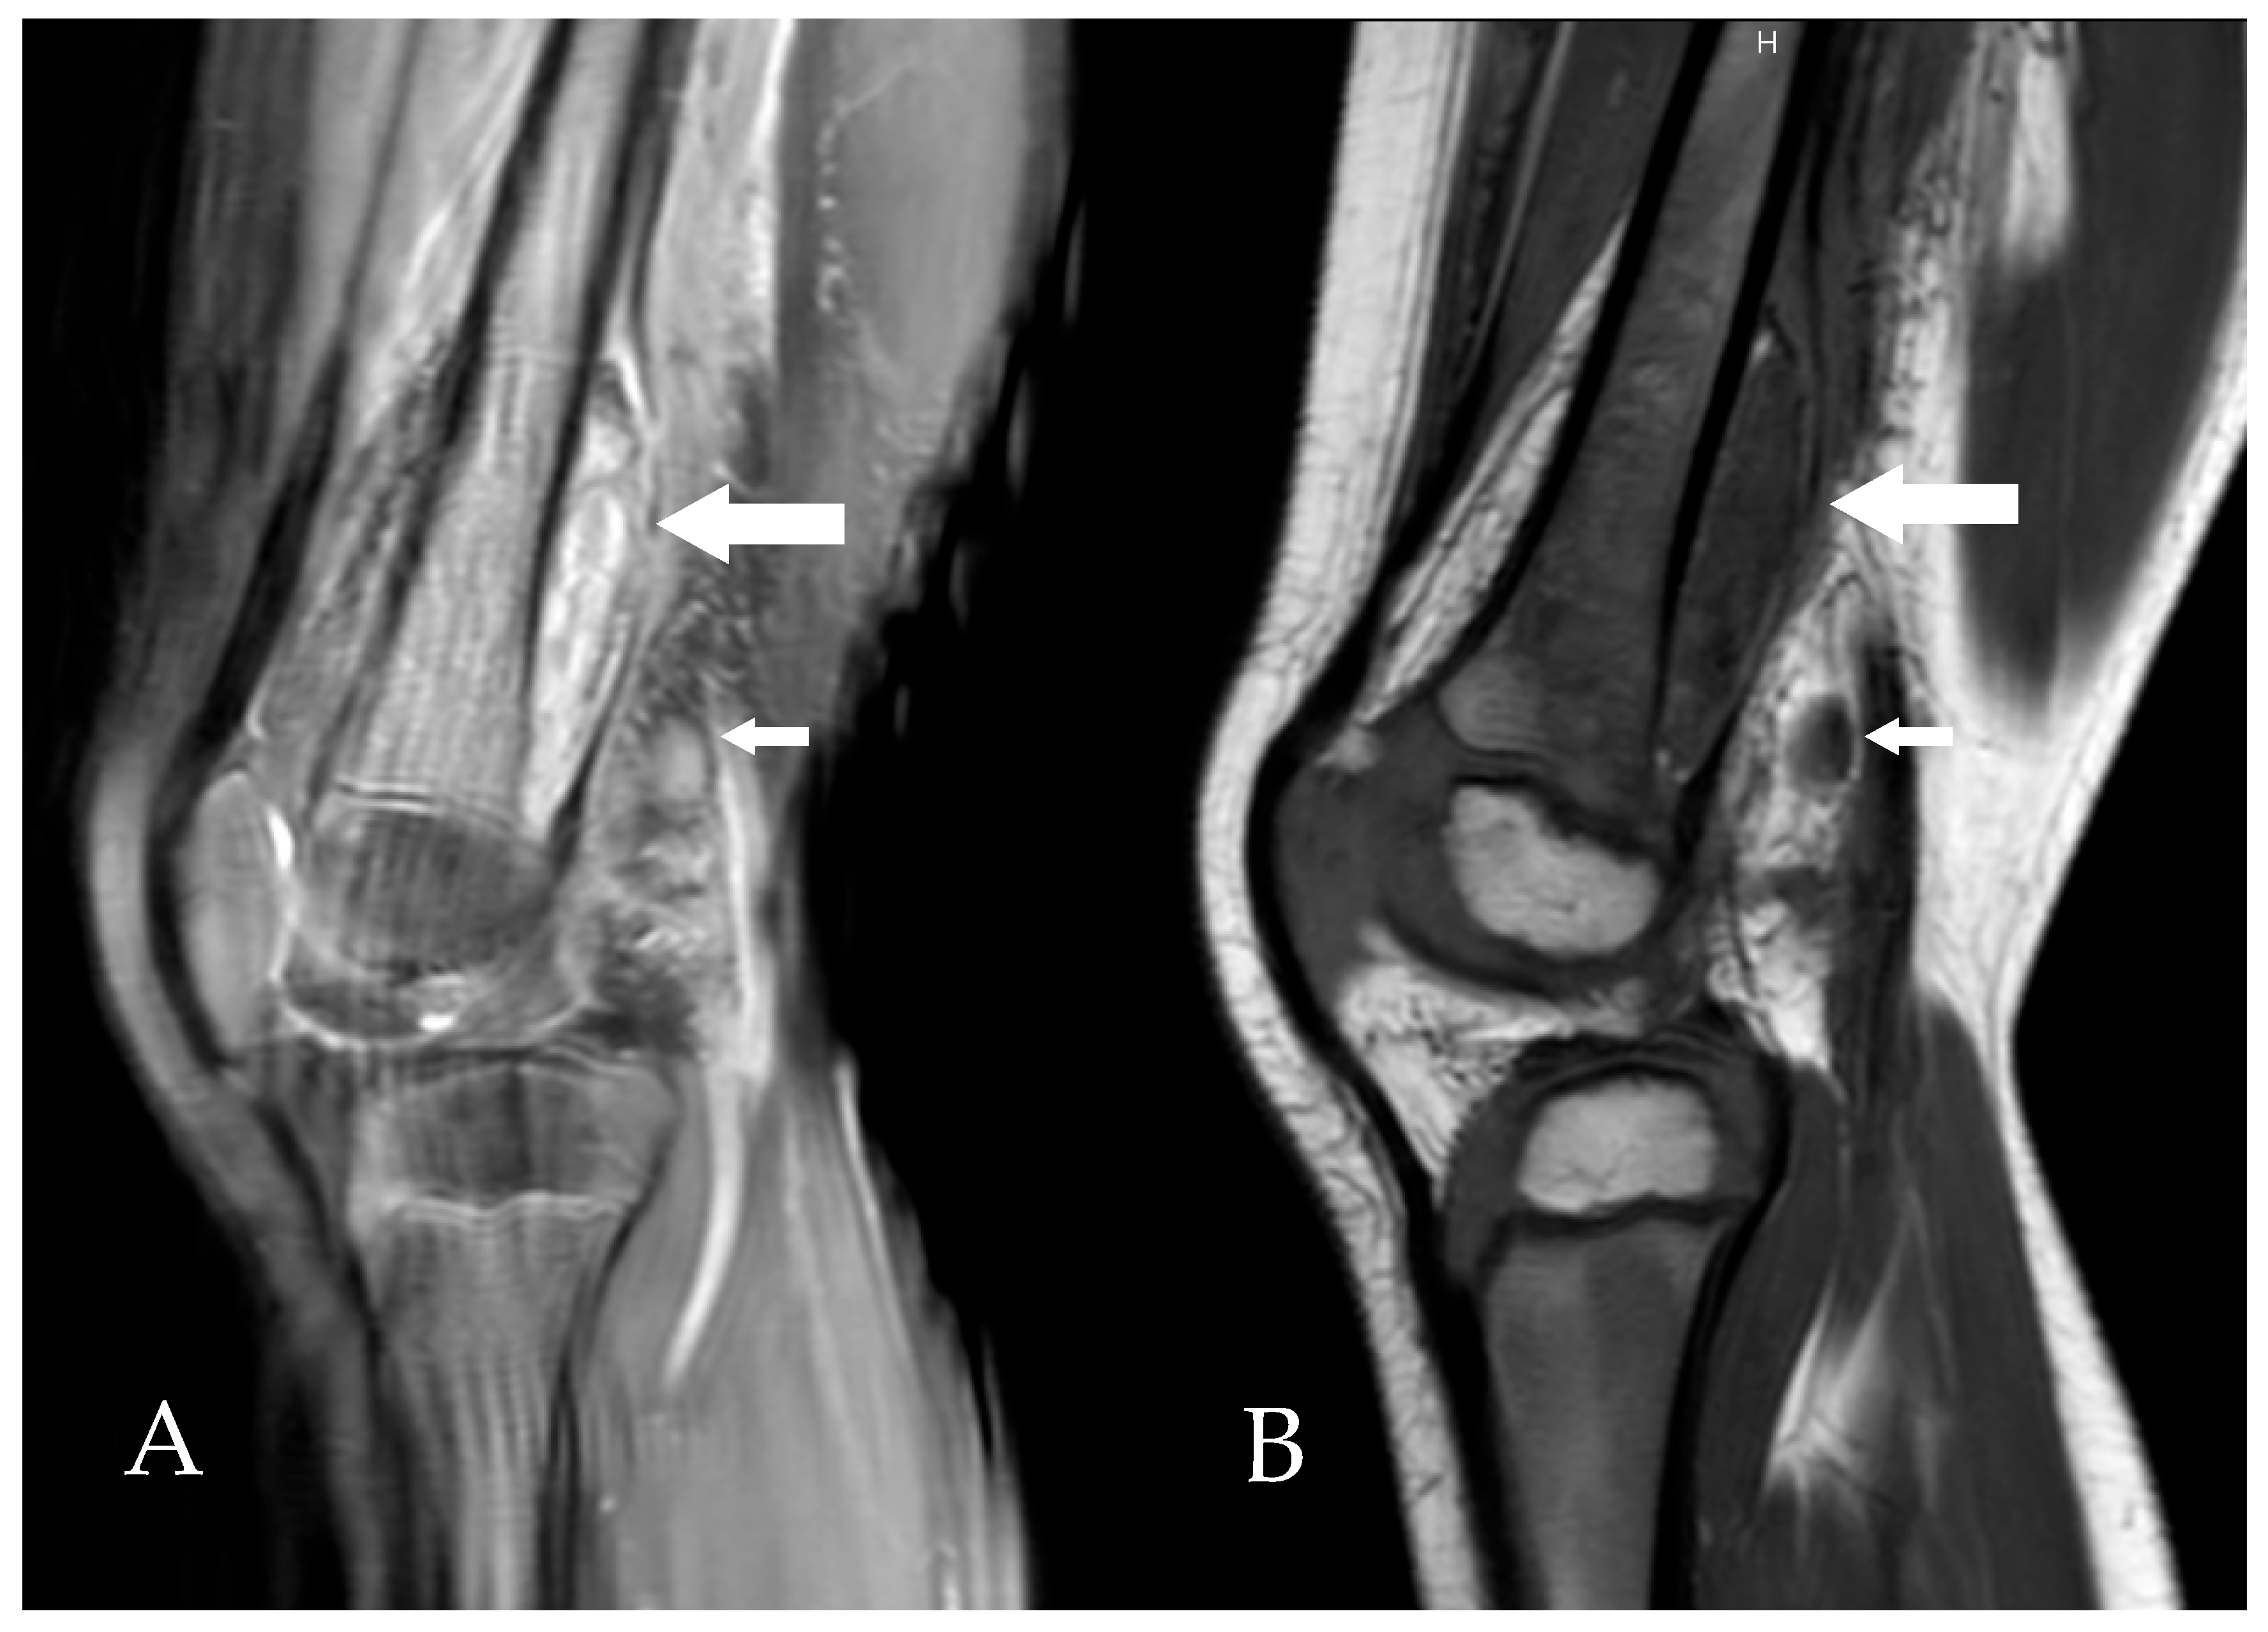

Imaging showed a very thin fluid layer in the right subquadriceps bursa on knee ultrasound. On day 5 of hospitalization, given the good clinical and biological evolution (reduced lameness and CRP decreased to 47 mg/L), oral amoxicillin for 7 days (100 mg/kg/day in 4 doses) was prescribed, and outpatient follow-up was arranged. Radiological evaluation was completed with an MRI of the knee, showing a subperiosteal collection in the distal third of the posterior part of the right femur (Figure 1).

Figure 1. Sagittal MRI slices of the right knee, T2-weighted (A) and T1-weighted (B), showing a heterogeneous subperiosteal fluid collection (large arrows) and the presence of lymphadenopathy (small arrows).